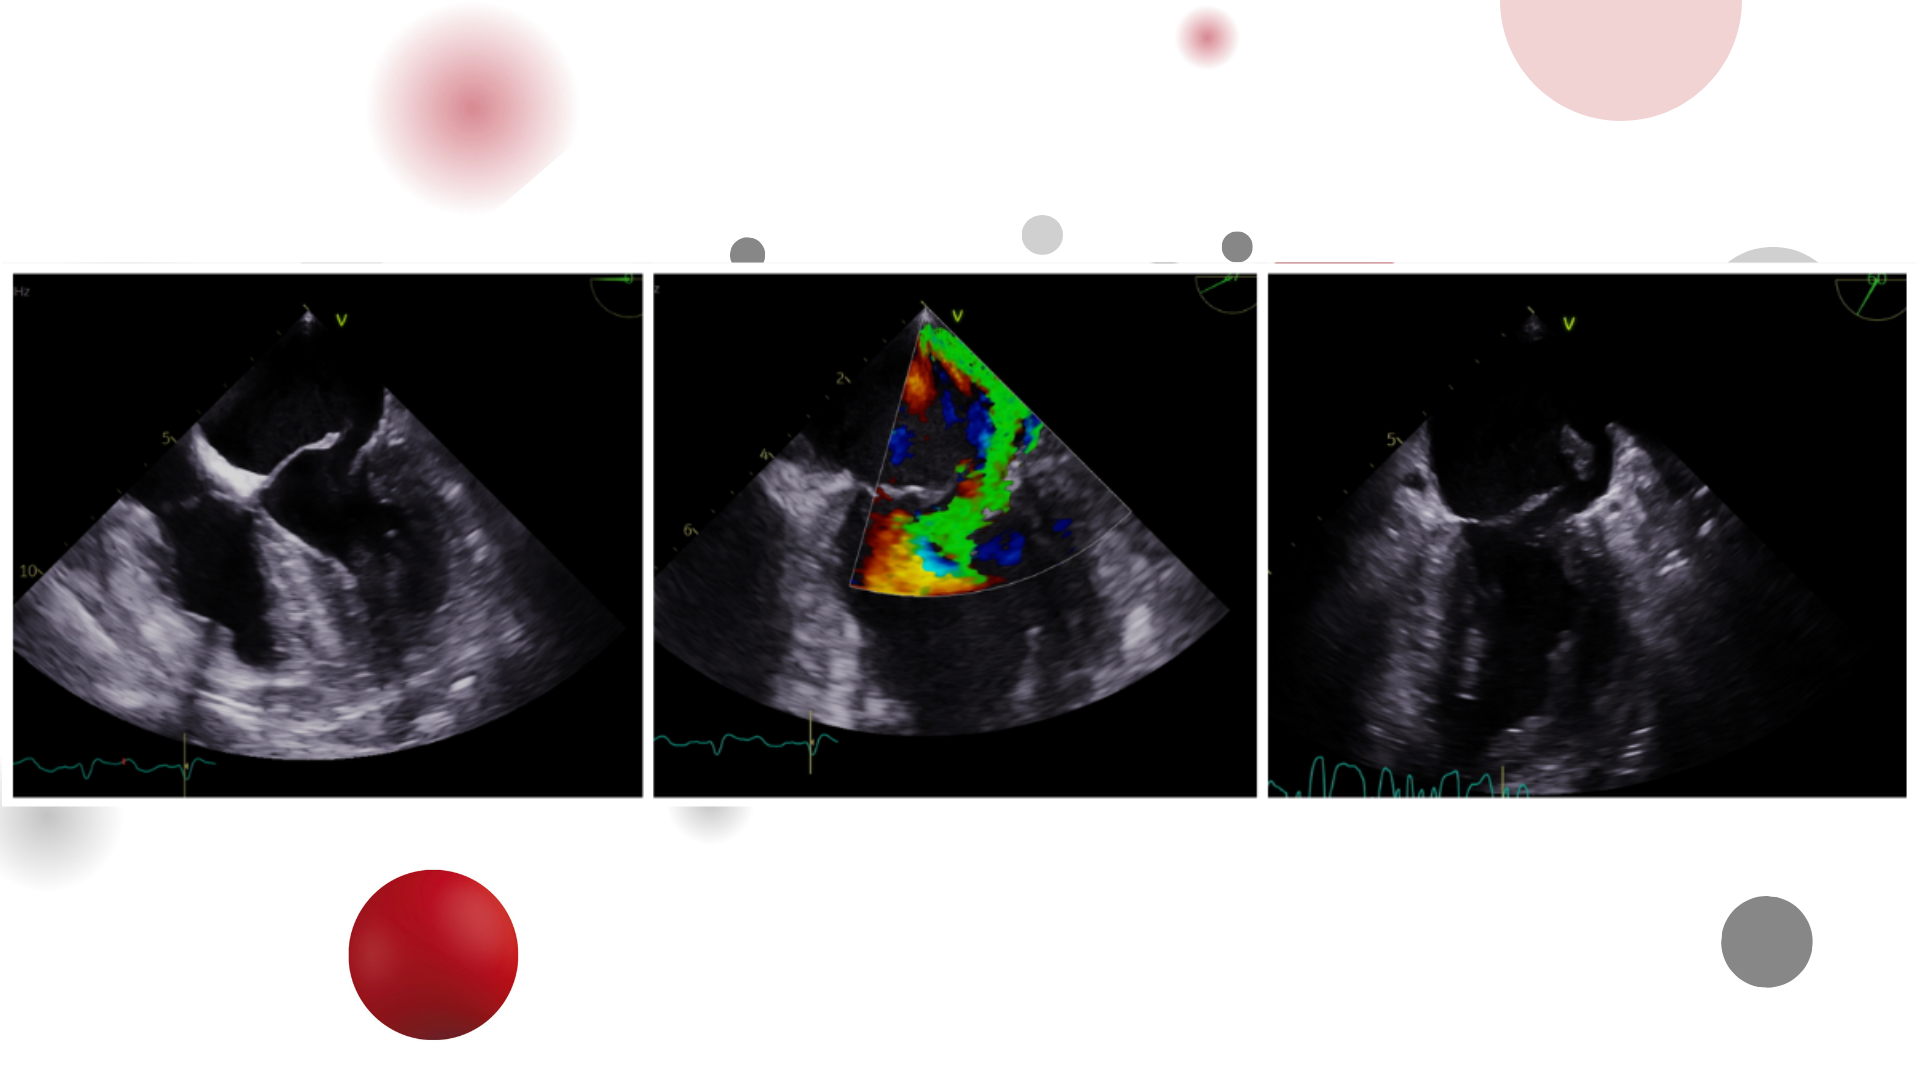

Image of the week 25 March 2026

Miss Joanna Kinga Rutka

Mr Youssef Sakan